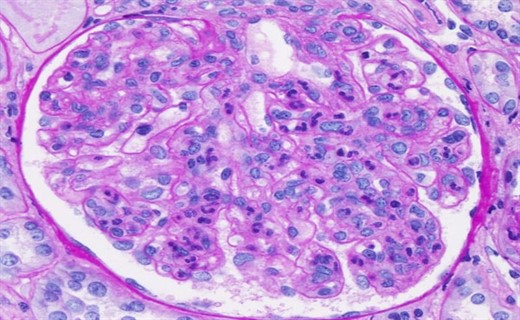

Механизм остро го диффузного гломерулонефрита